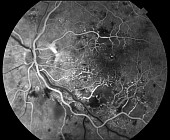

Fundus Fluorecein Angiography

Detailing Retinal Vessels

Diabetic Retinopathy |

Age-Related Macular Degeneration |

Central Retinal vein Occlusion |